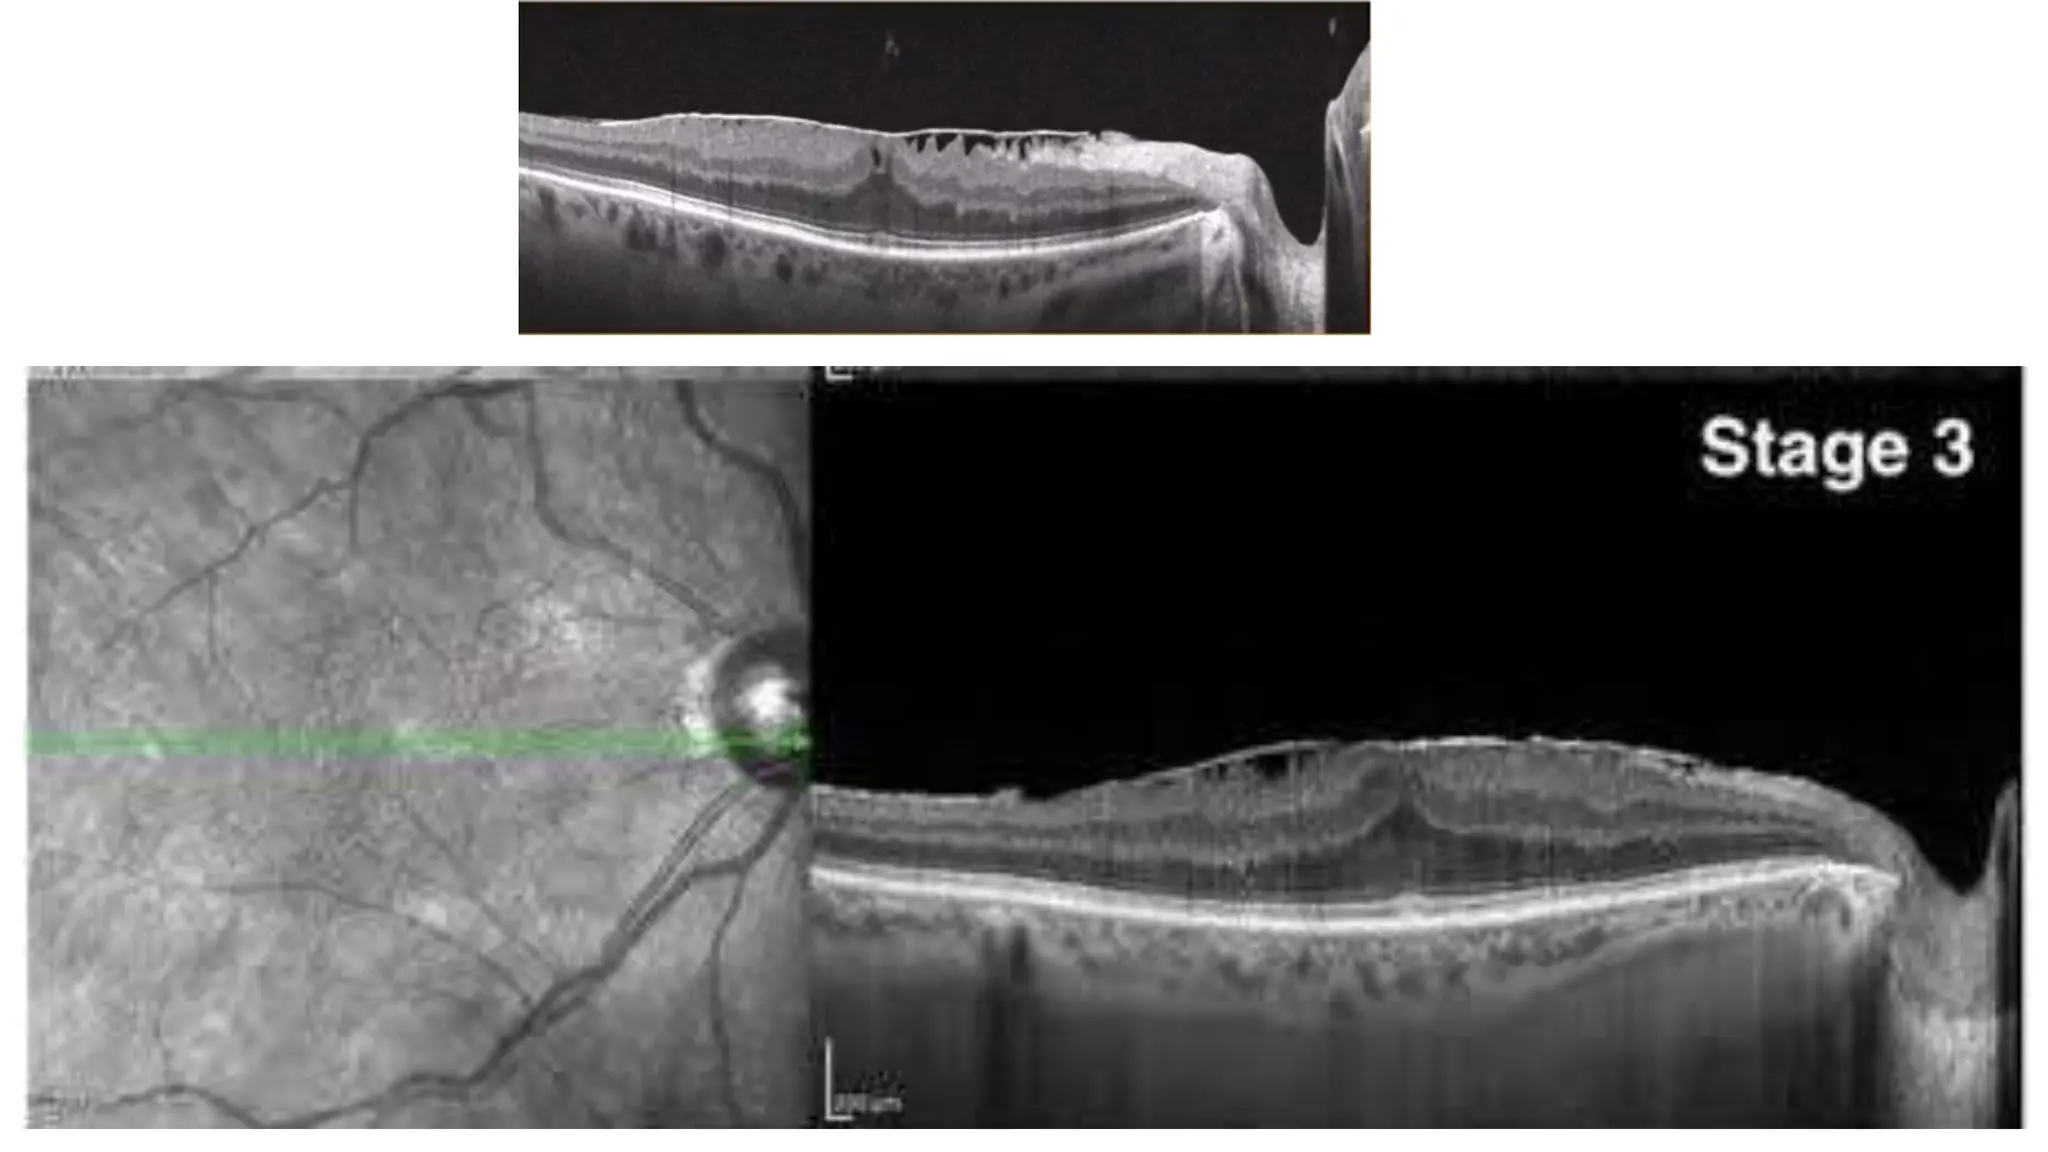

The document discusses various stages of posterior vitreous detachment (PVD) and associated ophthalmological conditions. It highlights the classification of PVD stages, including no PVD, paramacular PVD, and complete PVD, alongside related factors like traction and retinal issues. Key acronyms and terms relevant to diabetic retinopathy and retinal morphology are also mentioned.